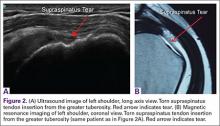

For rotator cuff tears, ultrasound is also comparable diagnostically with MRI (Figures 2A, 2B). In a prospective study of 124 patients, MRI and ultrasound had comparable accuracy for identifying and measuring the size of full-thickness and partial-thickness rotator cuff tears, with arthroscopic findings used as the standard.8 A 2015 meta-analysis published in the British Journal of Sports Medicine showed that the diagnostic accuracy of ultrasound, MRI, and MR arthrography in the characterization of full thickness rotator cuff tears had >90% sensitivity and specificity. As for partial rotator cuff tears and tendinopathy, overall estimates of specificity were also high (>90%), while sensitivity was as high as 83%. Diagnostic accuracy of ultrasound was similar whether it was performed by a trained radiologist, sonographer, or orthopedist.9